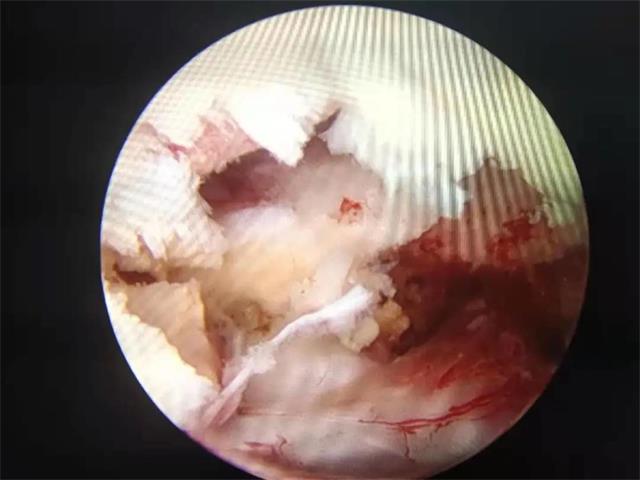

术中椎间隙终板处理,植骨准备。

术中融合器(Cage)植入